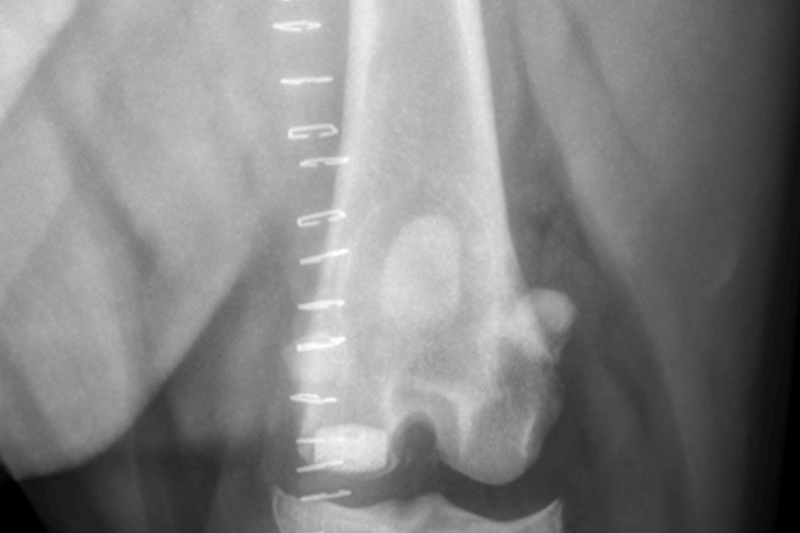

Hip Dysplasia in canines

Surgical Treatments of Hip Dysplasia